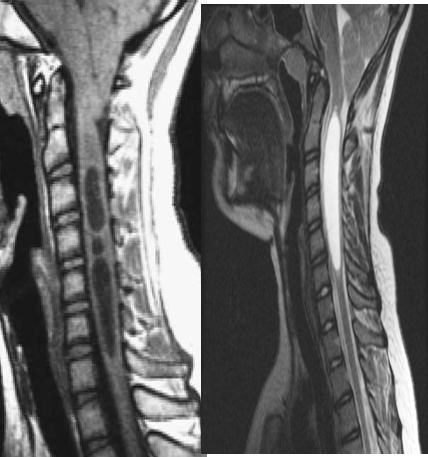

MRI:

Cystic area within the cord which appears of low signal at the T1WI and of high signal at the T2WI. No enhancement seen within the lesion at post-contrast study.